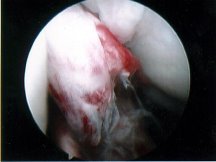

ACL Rupture

Exclude combined ACL+ Meniscal Detachment